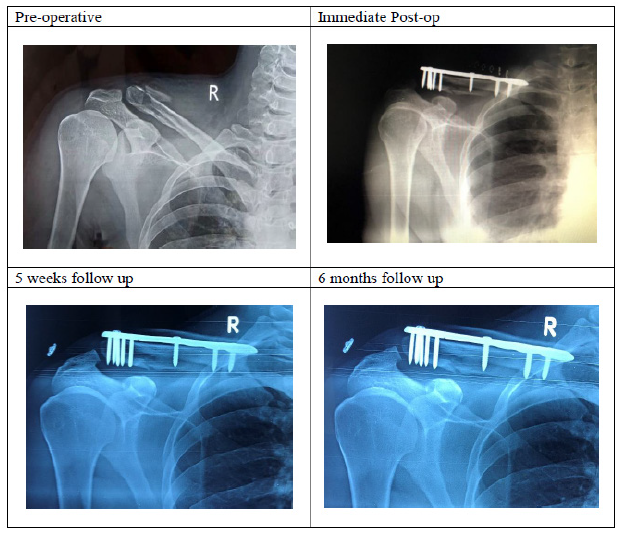

Figure 1:Lateral end clavicular fractures fixed with precontoured clavicular locking compression plate with broad lateral end.

Among 79 cases, 42 cases (53.16%) sustained injury due to road traffic accident, 21 cases (26.58%) fall from height and 16 cases (20.25%) due to trivial fall. There was no patient reported with bilateral clavicular fractures. All the patients were clinically and radiologically confirmed lateral end clavicular fractures (Neer’s types 2). According to Gustilo Anderson classification, type 1 compound cases were managed with tetanus toxoid and IV antibiotics pre-operatively. Type 2, 3a and 3b compound cases were managed with tetanus toxoid, IV antibiotic coverage and a thorough wound debridement. All cases underwent surgery with an average of 2.73±0.39 days. The mean duration of fracture union was 18.47±2.01 weeks. All the cases were followed up serially as per our protocol with serial clinical and radiographical examinations (Figure 2-4).

Figure 3:Radiographs of precontoured lateral clavicle locking compression plate with broad lateral end.